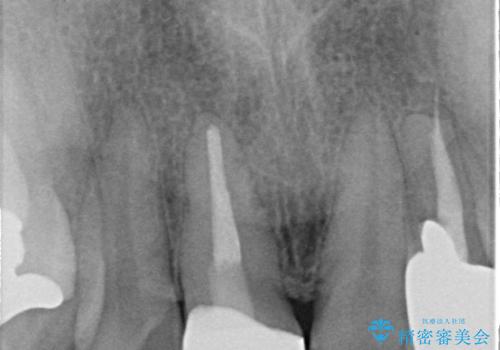

- 他院で装着された保険の前歯のかぶせ物が、他と歯と馴染まないので、自然な歯にしたいとのことで来院されました。

右上の1番目の歯の保険のかぶせ物と金属の土台を、ファイバーコアとオールセラミックにて再補綴する計画としました。